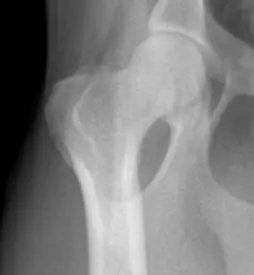

2. 고관절 구조와 수술의 원리

고관절은 대퇴골의 머리(볼)가 골반의 소켓에 맞물려 있는 구조로, 강아지의 뒷다리를 지지하는 중요한 관절입니다. 하지만 이 부위에 손상이 생기면 통증과 운동 제한이 심해지며, 보행이 어려워질 수 있습니다.

FHNO 수술을 통해 대퇴골 머리를 절제하면 볼-소켓 구조는 사라지지만, 시간이 지나면서 근육과 섬유 조직이 새로운 연결을 형성해 '거짓 관절' 역할을 하게 됩니다.